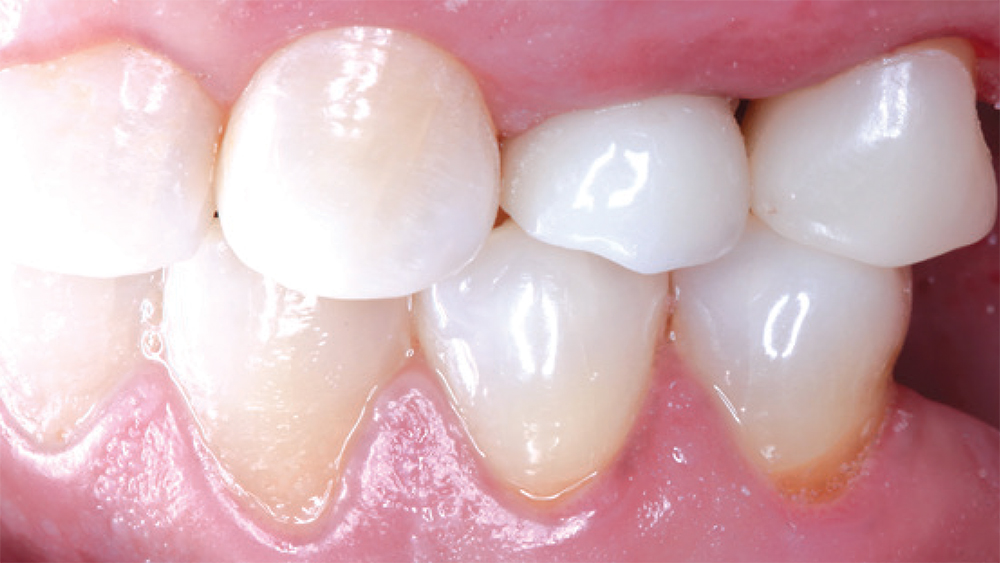

fractures premolar

fractured premolar

CAMouflage NOW used here to restore teeth #30 and #31, and blended extremely well with the adjacent natural teeth

CAMouflage NOW, which is manufactured in block form for the in-office fabrication of inlays, onlays and full-coverage crowns, was used here to restore teeth #30 and #31, and blended extremely well with the adjacent natural teeth.

– Clinical dentistry by Justin Chi, DDS, CDT